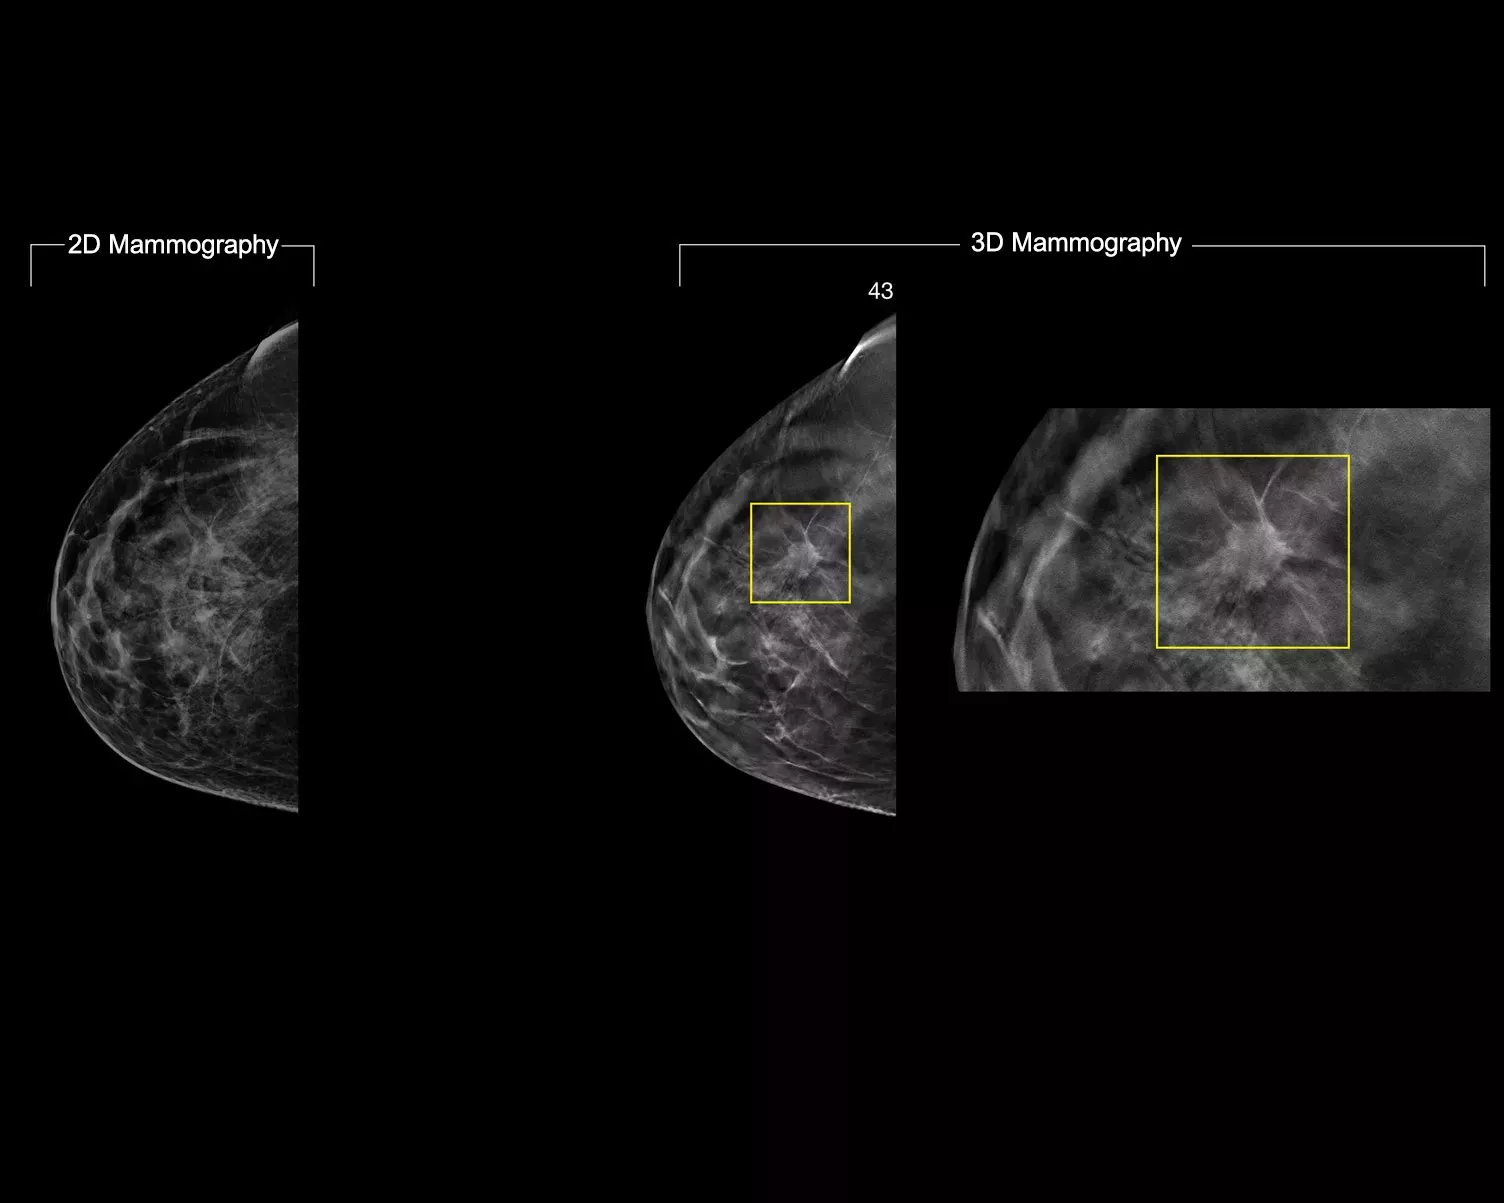

Un algoritmo de aprendizaje profundo diseñado para ayudar a los radiólogos en el diagnóstico y la detección del cáncer de mama1-3 en imágenes de tomosíntesis obtenidas con los sistemas Dimensions Mammography® de Hologic. El algoritmo localiza posibles lesiones compatibles con cáncer de mama, mediante la exploración de cada uno de los cortes del conjunto de imágenes de tomosíntesis. Las zonas sospechosas se resaltan para la lectura simultánea en la estación de trabajo del radiólogo y ayudar a la interpretación.

El algoritmo busca los tres grupos principales de lesiones sospechosas: calcificaciones, masas, densidades y distorsiones, y las combinaciones de estas lesiones. Los resultados pueden variar dependiendo de la estación de trabajo de lectura.